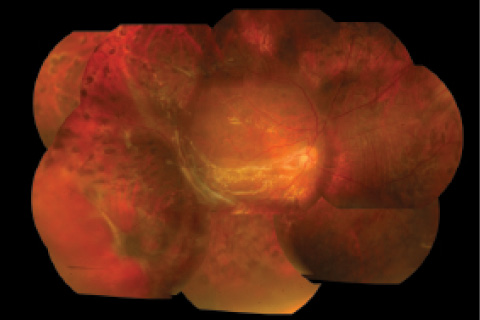

A 56-year-old woman was referred to our center with a history of a needle injury to her right eye (OD). Primary treatment had been given at a peripheral center. On examination, she had lid edema, chemosis, and subconjunctival hemorrhage OD. Additionally, the lens had been expelled into the superotemporal subconjunctival space (Figure 1). There was a mild hyphema, and the pupil was distorted and updrawn with vitreous in the anterior chamber. Fundus details were hazy due to vitreous hemorrhage. A dense suprachoroidal hemorrhage was noted on ultrasound (Figure 2). The patient’s visual acuity was light perception with faulty projection at this stage.

Figure 1. The lens of a 56-year-old woman has been expelled into the superotemporal subconjunctival space.

At 1 month follow-up, the patient was subjectively better, but she felt as though her visual acuity OD had slightly decreased since the initial recovery from the second surgery. On examination, the patient’s retina was well settled, with laser marks and inferior scarring evident. An epiretinal membrane (ERM) was seen on the macula extending from the inferior scar. It was felt that this membrane was the cause of her visual acuity loss to counting fingers at 3 m (Figure 3).

Figure 3. Photo montage shows an ERM on the patient’s macula OD extending from the inferior scar.